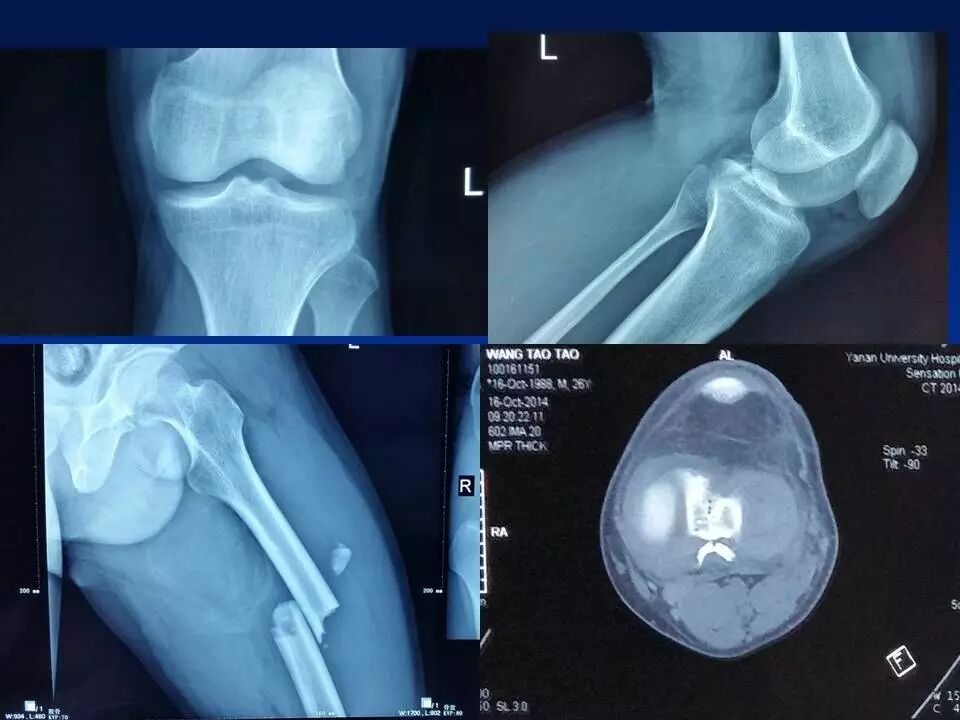

前十字韧带是膝关节重要的前向稳定结构,断裂后可以产生明显的膝关节不稳,严重影响膝关节功能,如果不及时治疗,关节出现反复扭伤,容易引起关节软骨、半月板等重要结构的损害,导致关节过早老化和骨关节病的发生。